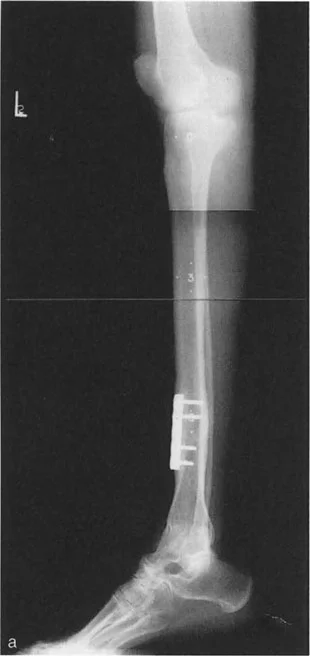

غالبًا ما يكشف التصوير بالرنين المغناطيسي عن تمزقات تنكسية أمامية في الغضروف الهلالي وآفات غضروفية متقابلة في المفصل الظنبوبي الفخذي الأمامي ناتجة عن الانحشار الأمامي المتكرر للركبة المفرطة التمدد. إذا عالج الجراح الركبة فقط (مثل استئصال الغضروف الهلالي أو قطع عظم الساق القريب)، فستفشل الجراحة لأن المحرك الأساسي للمرض - انكماش الكاحل - قد تم تجاهله.